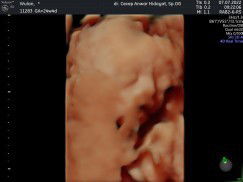

jk tidak bisa berubah bund, sebetulnya kromosom penentu jk sudah dibawa oleh pria sejak disemburkan sperma nya kalo pun berubah itu karna posisi janin sebelumnya masih menutupi saja

jk gak bisa berubah bun tp bisa jadi dokter yg salah memperkirakan. tp kalo usg 4d kn terlihat jelas sekali jd kemungkinannya kecil kalo salah prediksi